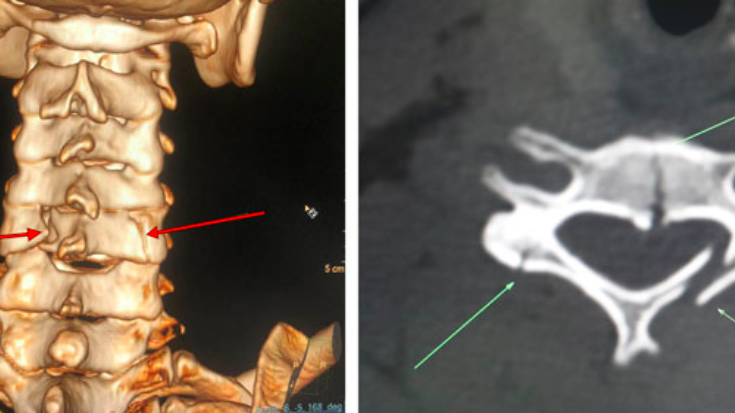

Chụp CT vùng cổ là phương pháp chẩn đoán hình ảnh hiện đại giúp phát hiện dị tật bẩm sinh, tổn thương, gãy xương, các khối u một cách nhanh chóng và chính xác, hỗ trợ hiệu quả trong việc chẩn đoán, điều trị.

Chụp CT vùng cổ là một kỹ thuật chẩn đoán hình ảnh tiên tiến, sử dụng sự kết hợp giữa công nghệ X-quang và máy tính để tạo ra hình ảnh chi tiết của cột sống cổ. Vậy, để đảm bảo kết quả chính xác nhất, bệnh nhân cần chú ý những điều gì trước, sau khi thực hiện chụp CT vùng cổ?

Chụp CT vùng cổ là một kỹ thuật hình ảnh cho kết quả nhanh chóng, đặc biệt hữu ích trong các tình huống cấp cứu. Bác sĩ có thể chỉ định chụp CT vùng cổ trong những trường hợp sau:

Chụp CT vùng cổ là một kỹ thuật quan trọng trong chẩn đoán điều trị các bệnh lý liên quan đến cột sống cổ, mang lại hình ảnh chi tiết và chính xác, hỗ trợ bác sĩ trong việc đưa ra các quyết định y khoa chính xác.

Kết quả chụp CT vùng cổ bình thường cho thấy không có tổn thương nào ở vùng cổ. Ngược lại, kết quả bất thường có thể chỉ ra các vấn đề như gãy xương, viêm khớp, hoặc dị tật bẩm sinh cột sống cổ.